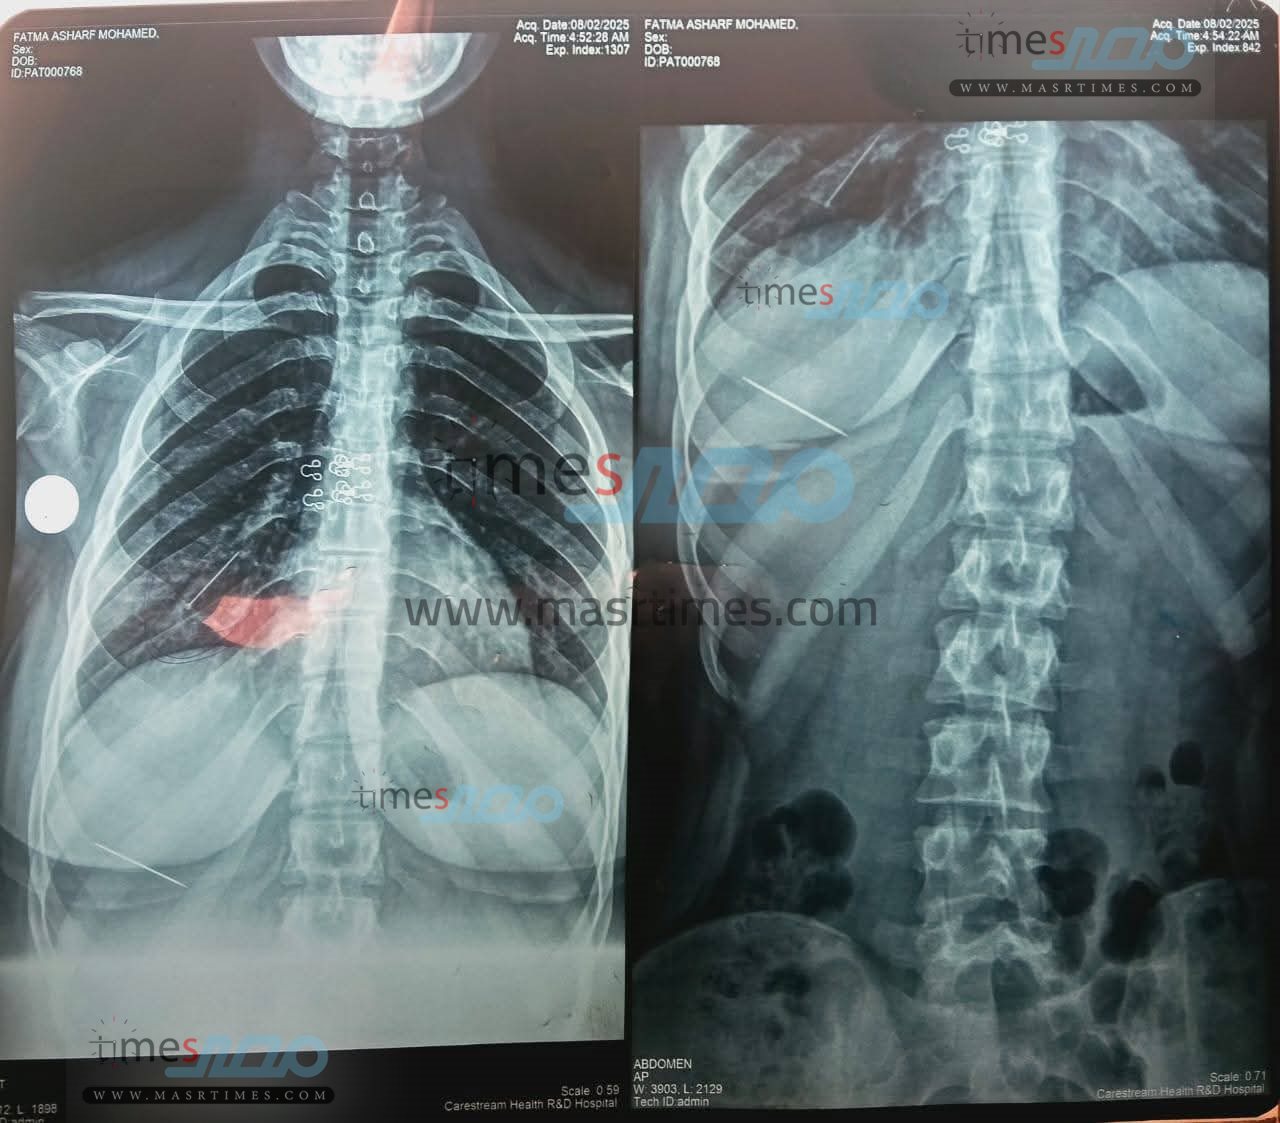

نجح فريق طبي بمستشفيات جامعة المنوفية، مساء اليوم الأحد، في إنقاذ حياة فتاة تبلغ من العمر 18 عاما، بعد ابتلاعها دبوس حجاب عن طريق الخطأ، ما أدى إلى اختناقهــا نتيجة استقراره داخل الشعب الهوائية بالرئة اليمنى.

وأوضحت إدارة المستشفيات الجامعية أن الفتاة وصلت إلى قسم الطوارئ وهي تعاني من آلام حادة بالصدر وسعال متواصل وصعوبة في التنفس، وعلى الفور أجريت لها فحوصات وأشعة أظهرت وجود دبوس معدني داخل الرئة، وآخر بالمعدة.

وتحت إشراف الدكتور محمد فهمي النعماني، عميد كلية الطب ورئيس مجلس إدارة المستشفيات الجامعية، قاد الدكتور أحمد عامر خميس، أستاذ الأمراض الصدرية، فريقا طبيا متعدد التخصصات من أقسام الصدر، والأنف والأذن، و التخدير، حيث جرى التدخل العاجل باستخدام منظار شعبي مرن تحت التخدير لاستخراج الدبوس من الرئة بنجاح وبدون مضاعفات.